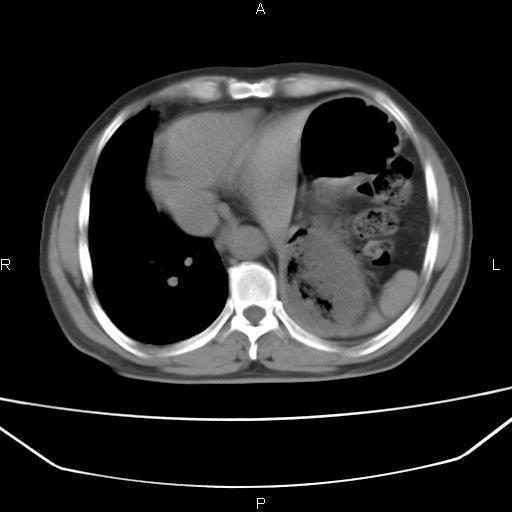

患者,男。50岁。近几日有咳嗽症状,无其他不适,既往病史无,考虑膈疝。请前辈们看看指导指导。

膈膨升,左下肺通气不良,膈肌好像还完整。

考虑左侧膈疝。

左侧膈疝。

符合隔膨升,膈肌较完整。